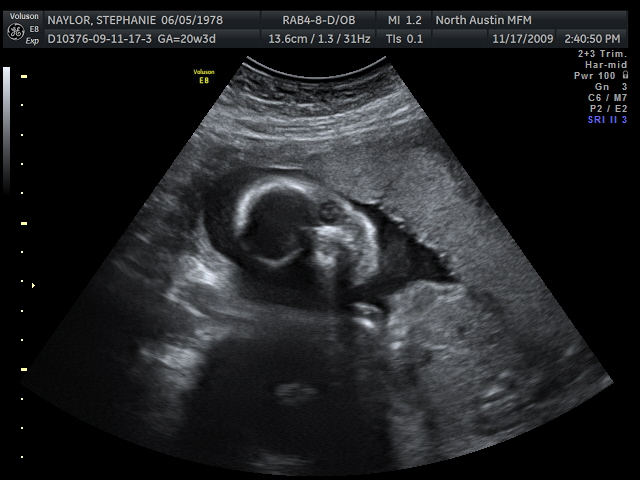

Here's Lumpy's little profile. Lumpy was moving around all over the place and really loves to touch his/her feet. I love all the pictures with the arms and legs.